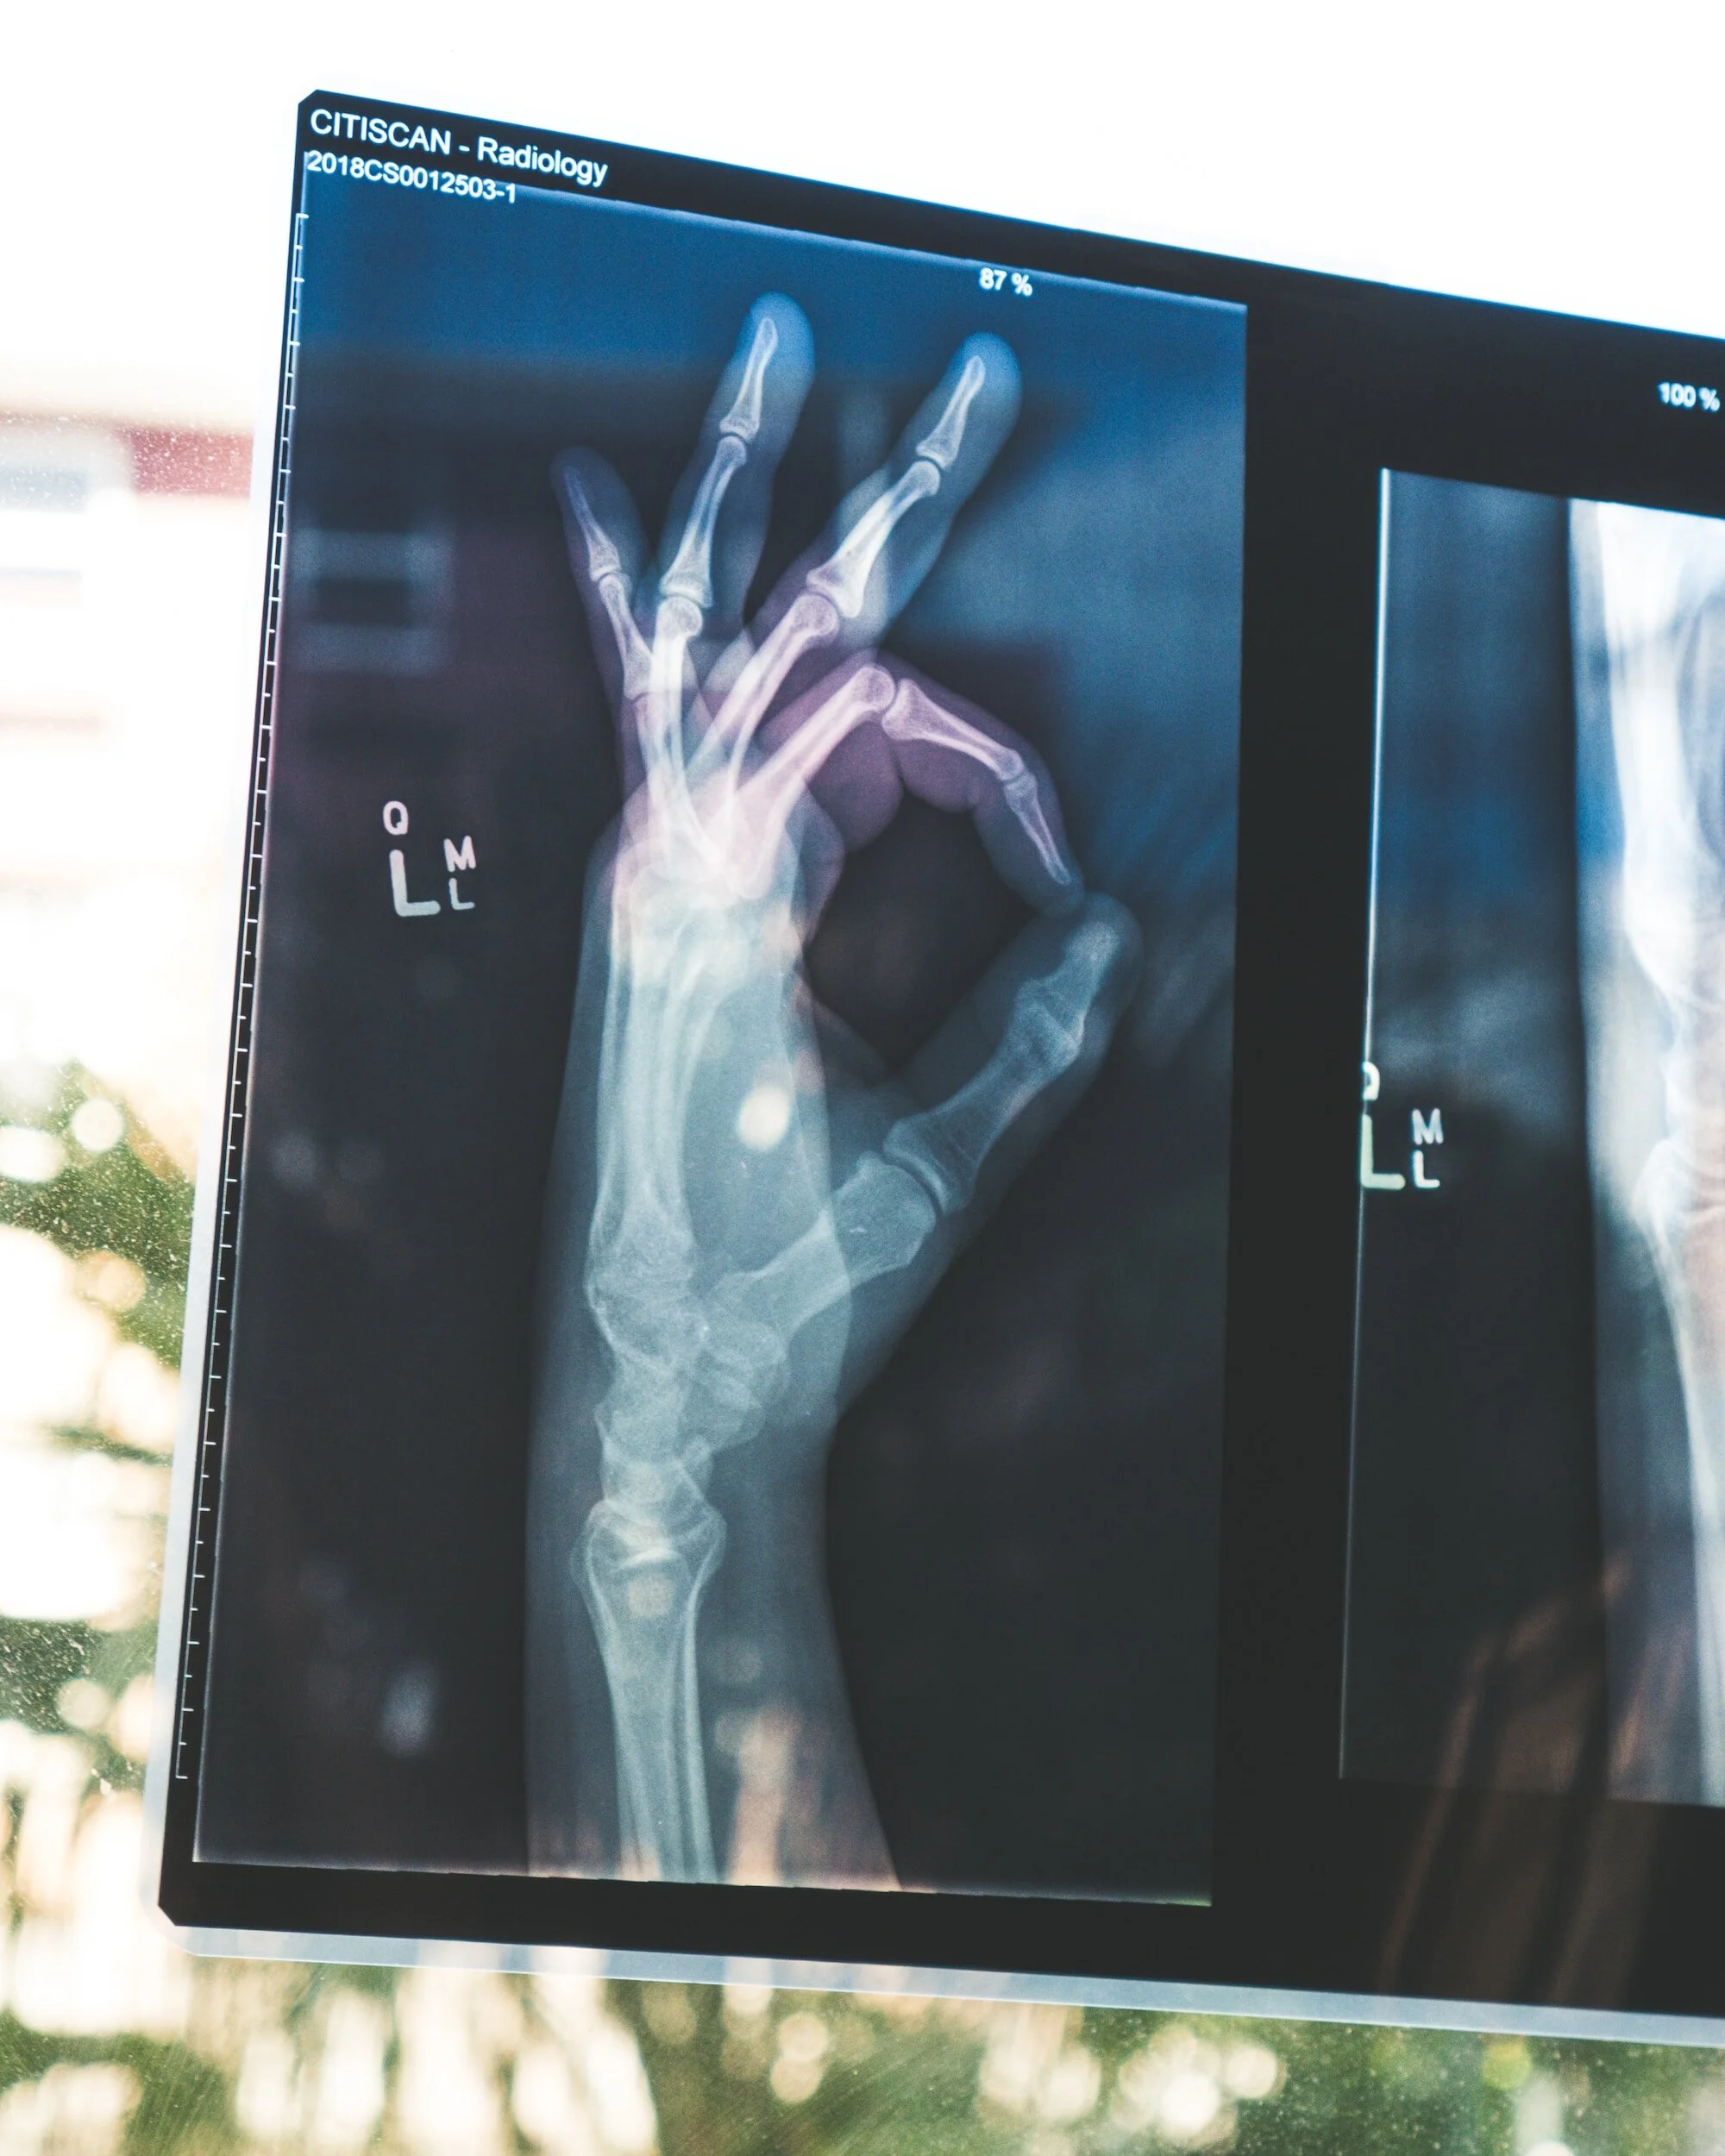

The musculoskeletal system is a multi-component system comprising of bone, muscle, connective tissue, tendons, ligaments, and associated nerves and blood vessels.

Its role is to provide support, shape, and stability for the body, protect organs, and to produce movement.

The common areas of pain are the lower back, upper limbs or neck, followed by lower limbs.